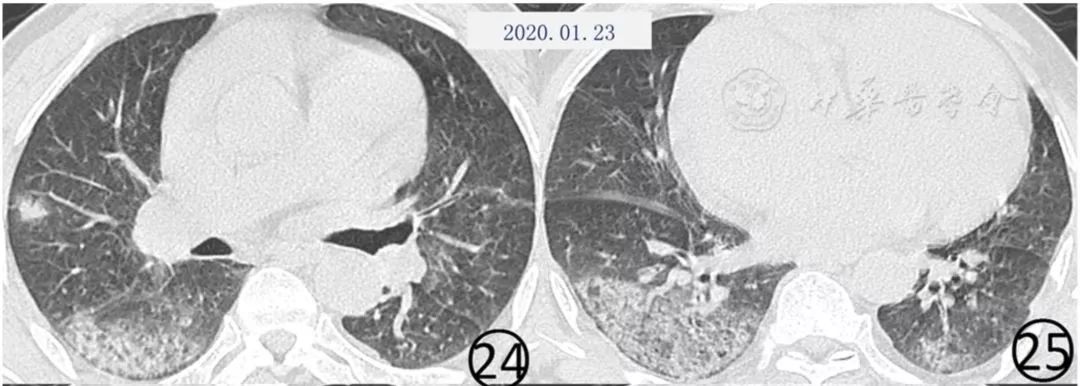

部分患者病变可以在较短的时间内演变为纤维化的索条影(图24,图25,图26,图27),这种纤维化表现是否为病变逆转的特点,仍有待于资料的进一步积累。

图24~27 男,60岁。首次(图24,25)CT平扫肺窗显示,两肺可见大片状磨玻璃阴影,右肺下叶前段有结节和晕征,新型冠状病毒核酸检测阴性。5 d后(图26,27)CT平扫肺窗显示,大片磨玻璃阴影有吸收,但是出现新发的斑片状磨玻璃阴影,其内有血管增粗,斜裂局限性增厚,两下肺有纤维化形成,其内可见扭曲的细支气管充气征